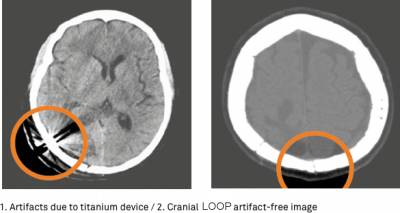

アーチファクトを引かないので画像診断に優れる

PEEK製のためCT、MRI撮影時のアーチファクトがない